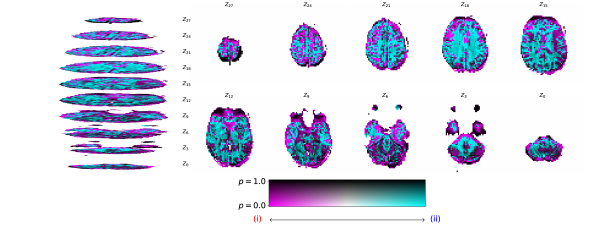

Converging to retrieve near scalp haemodynamical activity. One interesting phenomena that was observed by propagating relevances from the latent representations of the fMRI instance, , to the input, , was that the relevances in sub-cortical areas were neither positive nor negative, yielding residual relevance, as seen in Figure 6. This later observation suggests that haemodynamical activity from these areas does not significantly aids the targeted synthesis. Recall that the regularization term, , is used with the latent EEG and fMRI representations. This is in accordance with the fact that the retrievable information is in its majority next to the scalp, where the electrodes are placed. de Beeck and Nakatani [15] discuss how high frequencies are not able to travel significant distances with obstacles, such as white matter and the scalp, in between. We also report negative relevances on the visual cortex and positive relevances on the occipital and prefrontal lobes. Please note that negative and positive relevances represent relevant features, whereas when one has zero relevance, it means a feature was not relevant for the task. Daly et al. [8] found that neuronal activity retrieved from EEG can reflect the haemodynamical changes in subcortical areas. Here we claim that haemodynamical activity information in areas next to the scalp are relevant to learn the shared latent space.